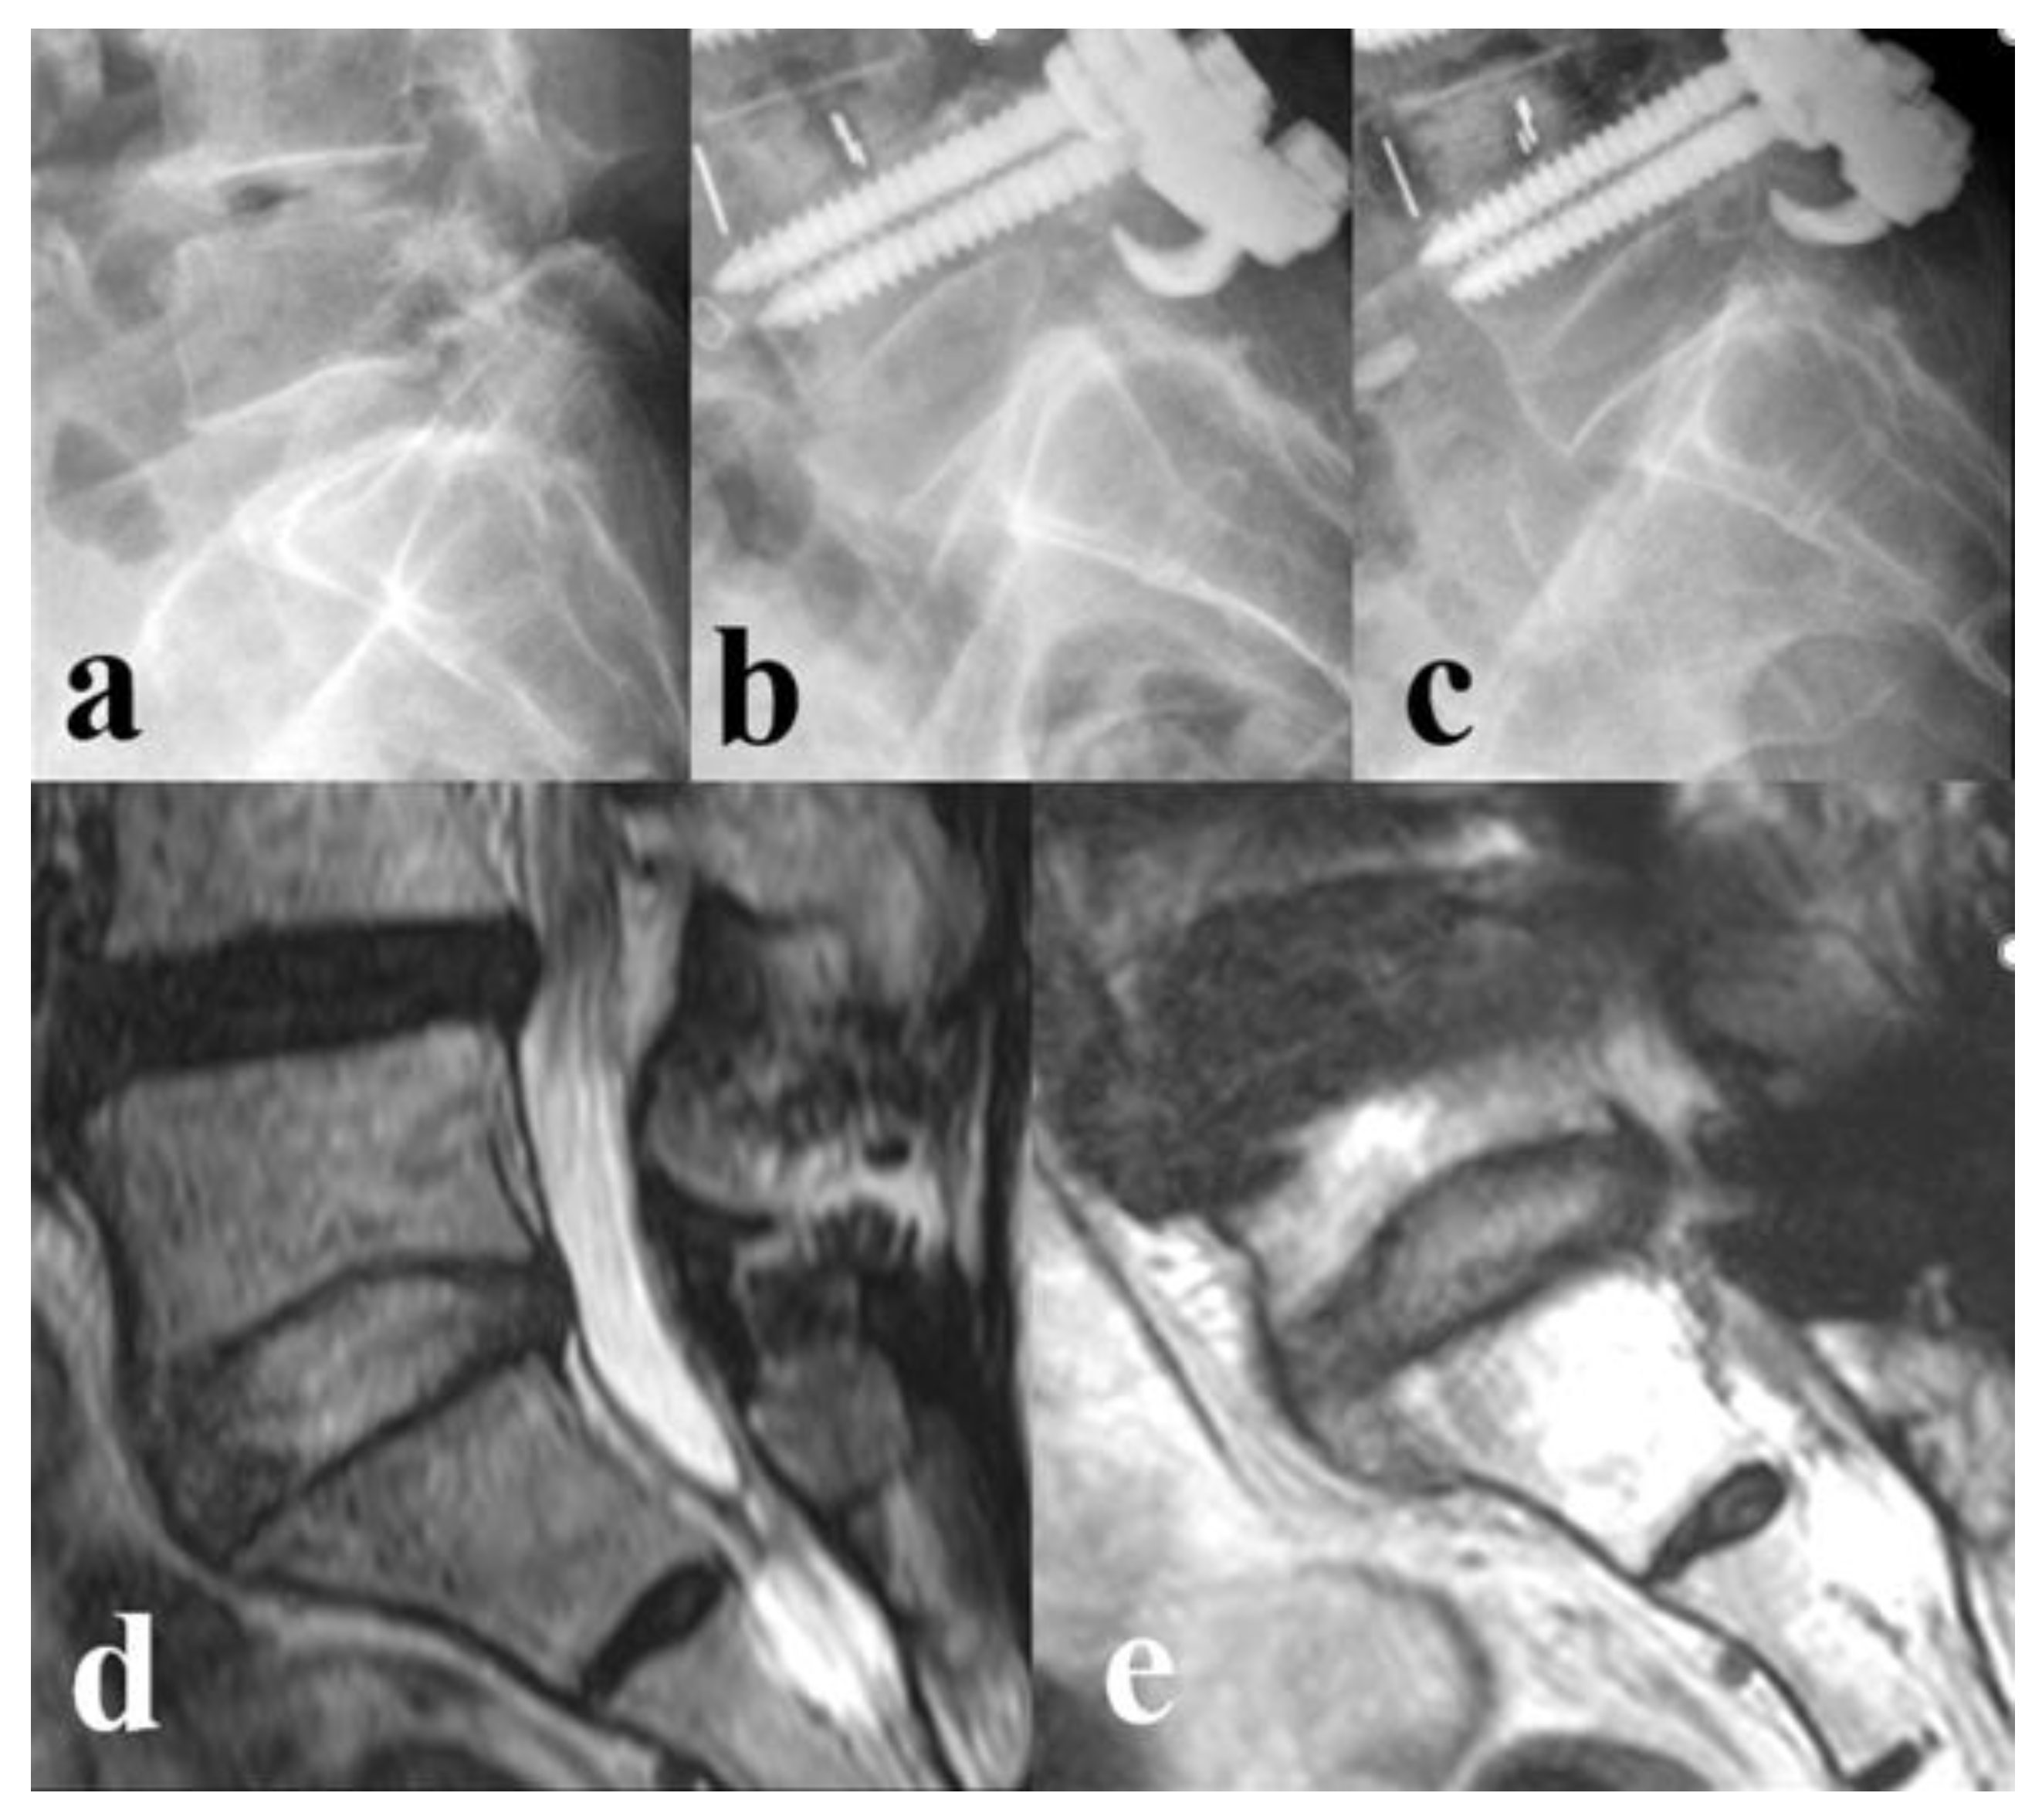

Figure 3. Standing lateral radiographs and MRI status in L5-S1 level of a 67-years old female. (a) Preoperative L5-S1 status. (b) Immediate postoperative L5-S1 status. (c) 2 years follow-up L5-S1 status, shows that there is little decrease in disc height compared to the immediate postoperative status. (d) Preoperative L5-S1status, showing Pfirrmann grade 1. (e) 2 years follow-up L5-S1 status, showing Pfirrman grade 2.

Disc degeneration, retrolisthesis, or stenosis in adjacent segments are well-known risk factors for adjacent segmental degeneration (ASD) [13,14]. Cannizzaro et al. [7] reported the risk factor of ASD according to Pfirrmann grade in disc degeneration of adjacent segments, and based on this, we classified Pfirrmann grade 1, 2, and 3 as ‘healthy status’ and grade 4 and 5 as ‘degenerated status’ in this study. Previous studies [15,16] reported that the rates of post-surgical L5-S1 disc degeneration were approximately 58% and 69% following long-level surgery that stopped at L5. In the present study, 75% of patients in Group II experienced post-surgical L5-S1 disc degeneration (from ‘healthy status’ to degenerated status’) within two years of surgery, which was a higher proportion than that reported in previous studies. We believe that our worse results were due to the fact that the patients in our study were elderly (72.86±6.20 years of age), had a high BMI (26.86±4.67 kg/m2), and had a long fusion level; these are all known preoperative risk factors for disc degeneration [17]. Previous studies demonstrated that the addition of laminar hooks in a pedicle screw-rod construct increased pullout resistance and contributed to load sharing or stress distribution between the instrumented segment and the adjacent level without affecting the segments with normal motion [8,9,18]. In addition, laminar hooks have a less rigid attachment to the instrumented vertebrae, thus allowing the spine to adjust and form a smooth transition with the adjacent segment. Laminar hooks also help to counteract dorsally directed, craniocaudal, and mediolateral forces on pedicle walls during surgical correction [9]. In addition, laminar hooks increase the bone-implant contact surface area, thus facilitating resistance against dorsally directed forces at the distal segment [18]. Collectively, our results showed that the L5 laminar hook prevented subsequent L5-S1 disc degeneration when used for long-level fusion (Figure 3).